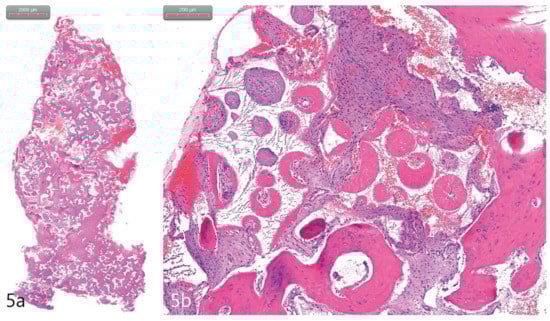

Figure 5. (a). The core biopsy with H&E stain. (b). The newly generated bone was well-observed around the bone substitute particle. The new bone contained osteoids, osteoblasts, and osteocytes. Immature osteoid tissue was distributed between bone grafts (H&E stain).

The case report presented here demonstrates no clear perforations with uneventful healing for the patient. Immediately following the surgery, CBCT analysis of the implant placement and bone augmentation demonstrated adequate elevation and grafting in the lateral nasal wall of the inferior meatus (Figure 3a,b). Figure 3a specifically demonstrates a well-defined periphery of the grafted site along the implant placed at site #4. The implant at site #2 was placed utilizing the transcrestal approach and depicts partial bony engagement of the lateral wall (Figure 3b). The surgical site healed uneventfully and no early or late complications were documented. Six months post-surgery, radiographic and clinical examination revealed stable implants engaged with the augmented bone during the uncovering. The bone biopsy harvested at implant uncovering and the placement of healing abutments were evaluated morphometrically. The core-stained slides were examined and depicted in entirety in Figure 5a, at 1× resolution. Figure 5b at 10× resolution, provides a detailed view of the newly formed bone and residual calcium phosphate particles. The newly depicted bone demonstrates osteocytes encased within and associated active osteoclast and osteoblasts cells. The actively remodeled sites are flanked by osteoid deposits and residue calcium phosphate particles. Histologically, the site does not demonstrate any necrotic bone, bacterial debris, or invasion. The site demonstrates active bone remodeling, indicating vital bone undergoing bone turnover where the biphasic calcium phosphate is eventually resorbed and replaced by new bone. Furthermore, clinical and radiographical observations reveal no associated complications such as marginal bone loss around the implants placed at sites #2 or #4 or soft tissue ingress, etc. (Figure 6a–c). The patient’s airways continue to remain patent, with no clinical complication or masticatory problems reported in subsequent follow-ups.